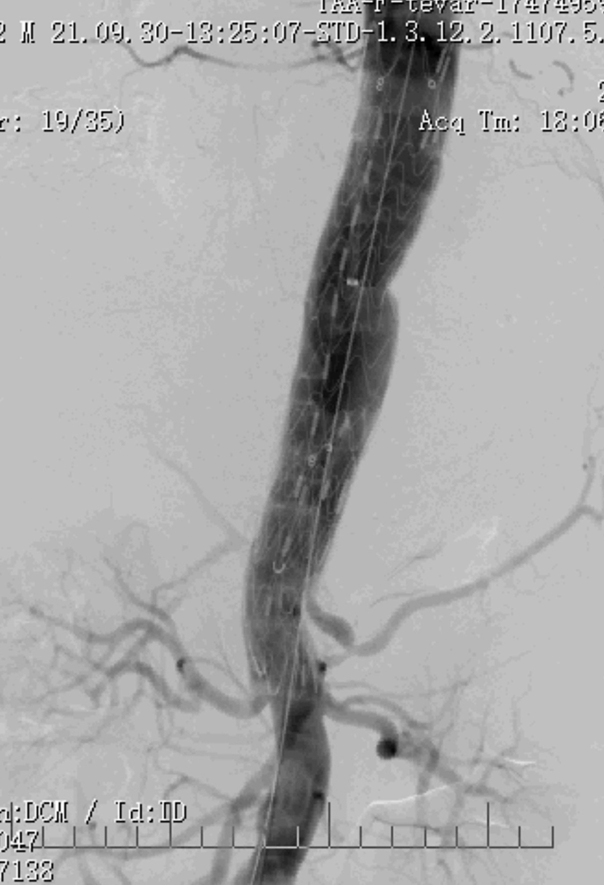

病例1 两开窗:

病例2 四开窗:

手术时间382分钟

造影剂用量320ml